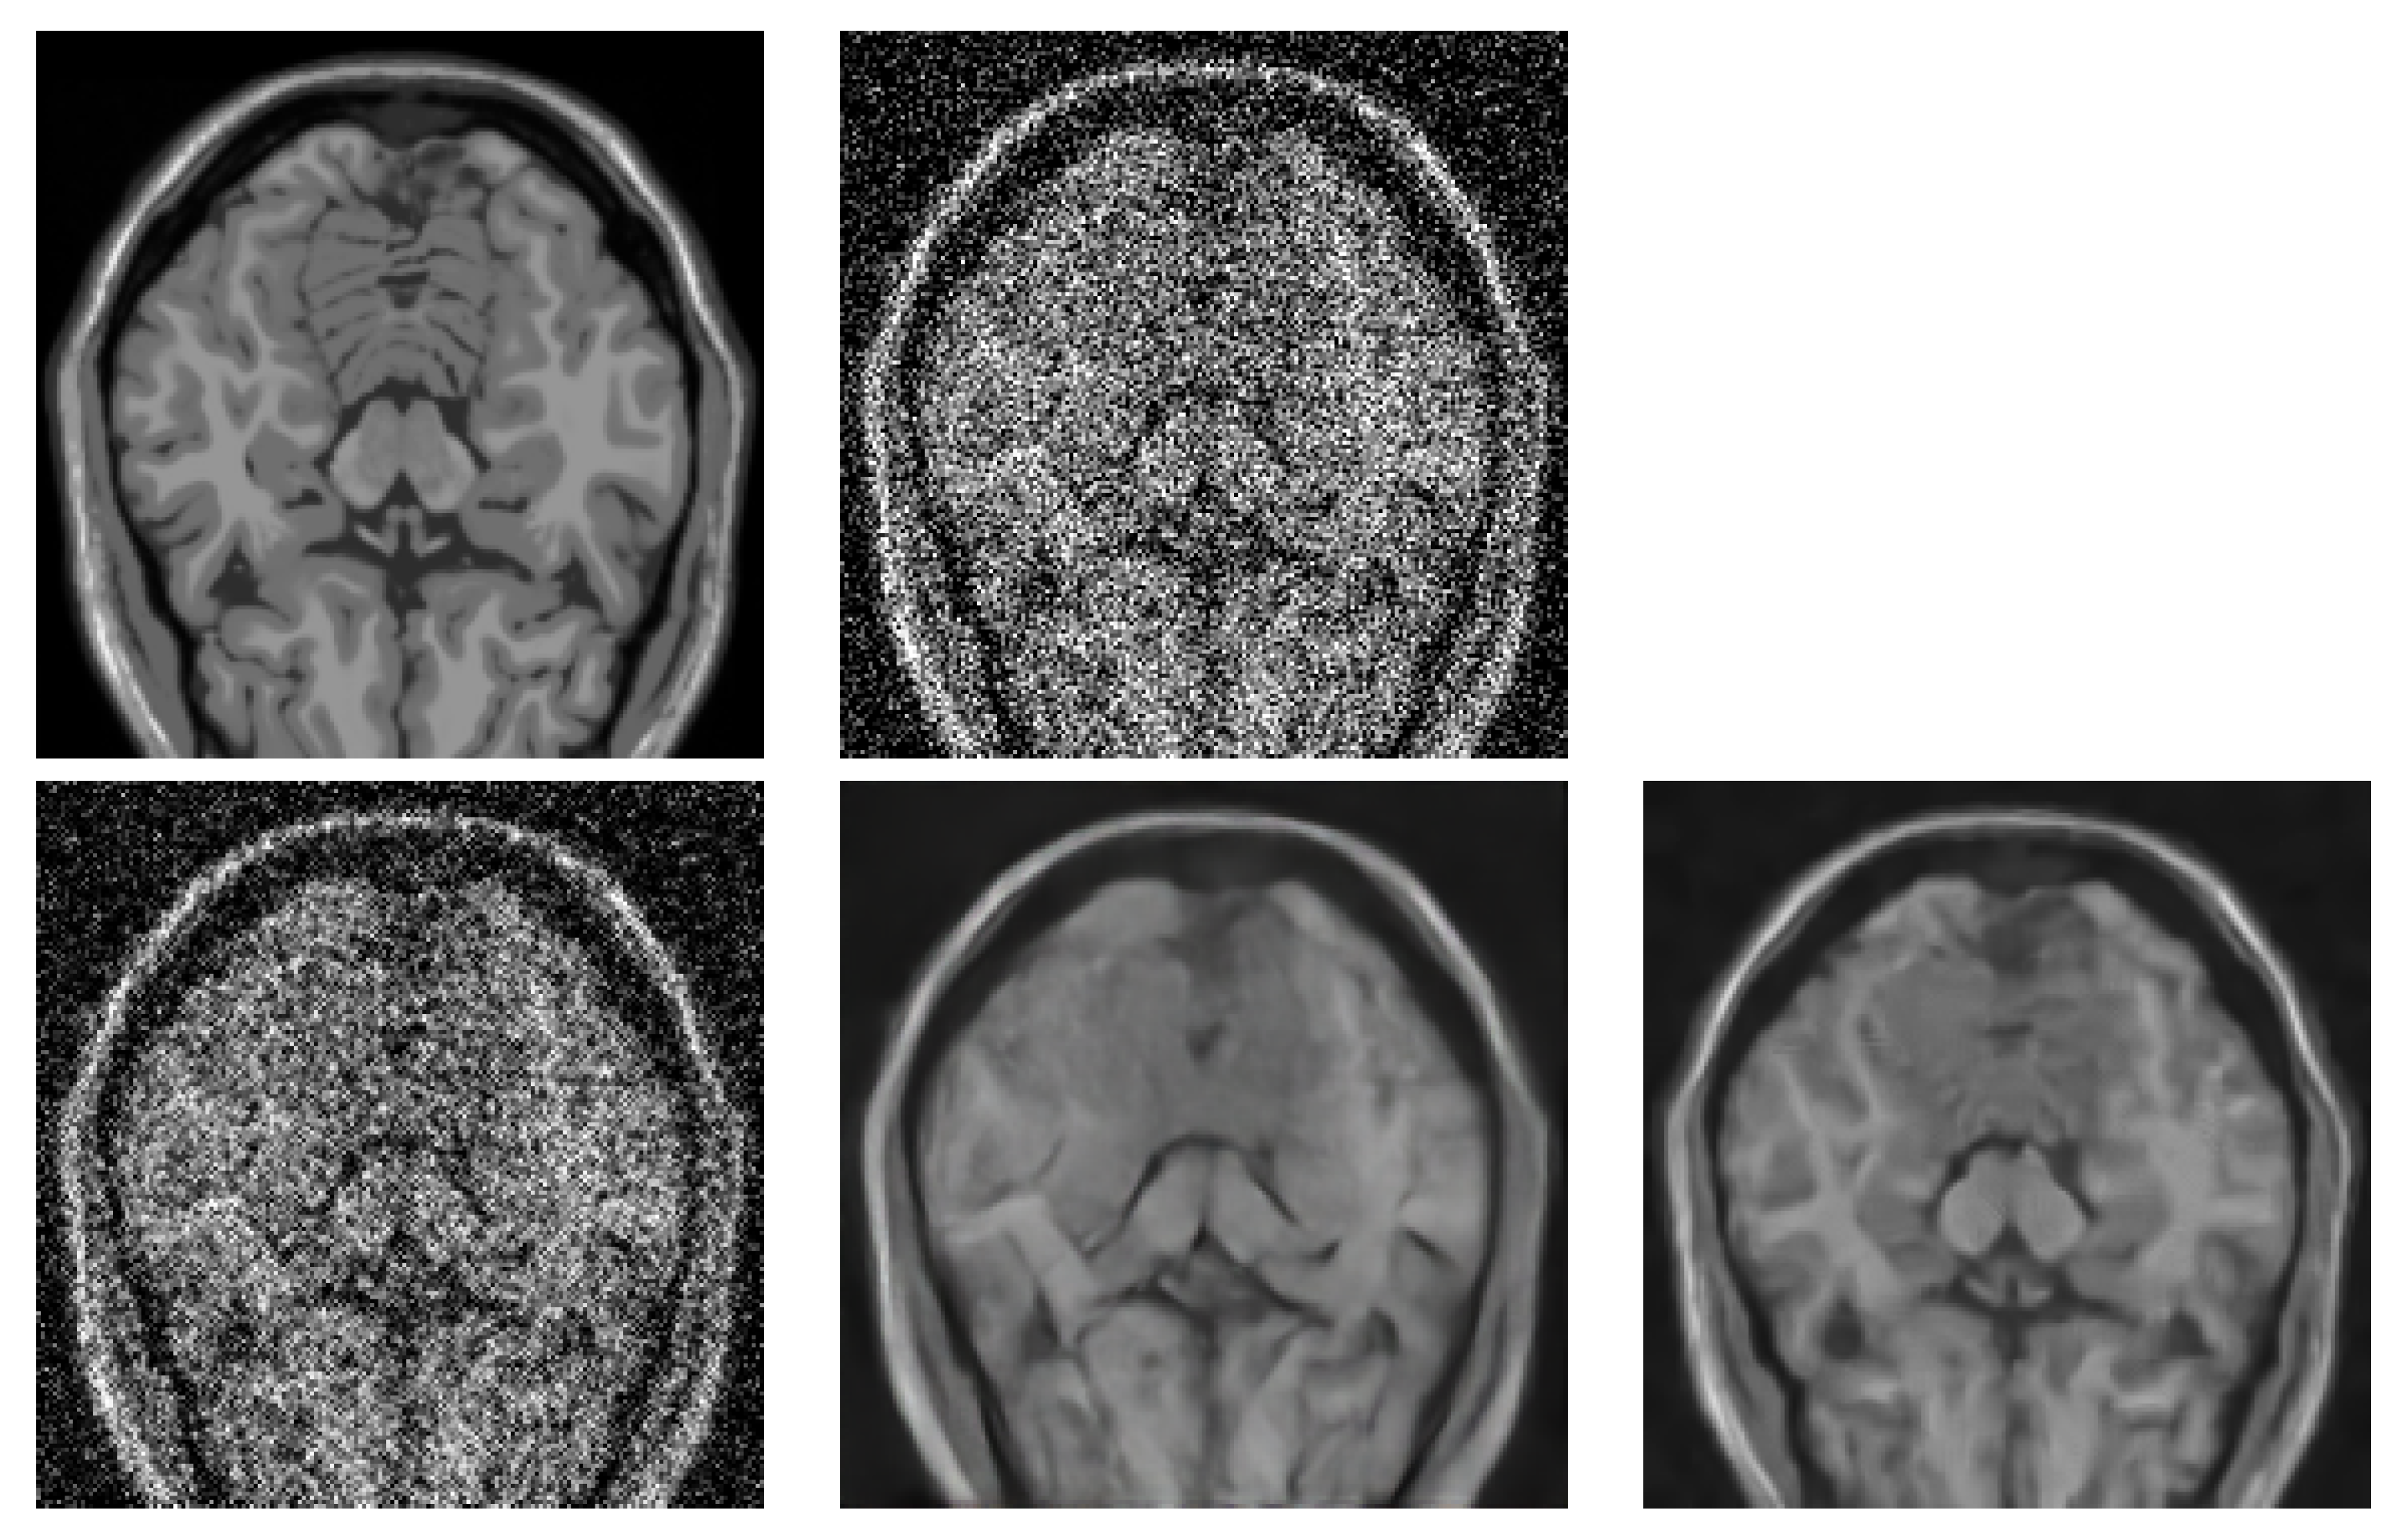

- Comparison of the algorithm with DL-based approaches.

- Testing the algorithm as a pre-processing stage before volume rendering.